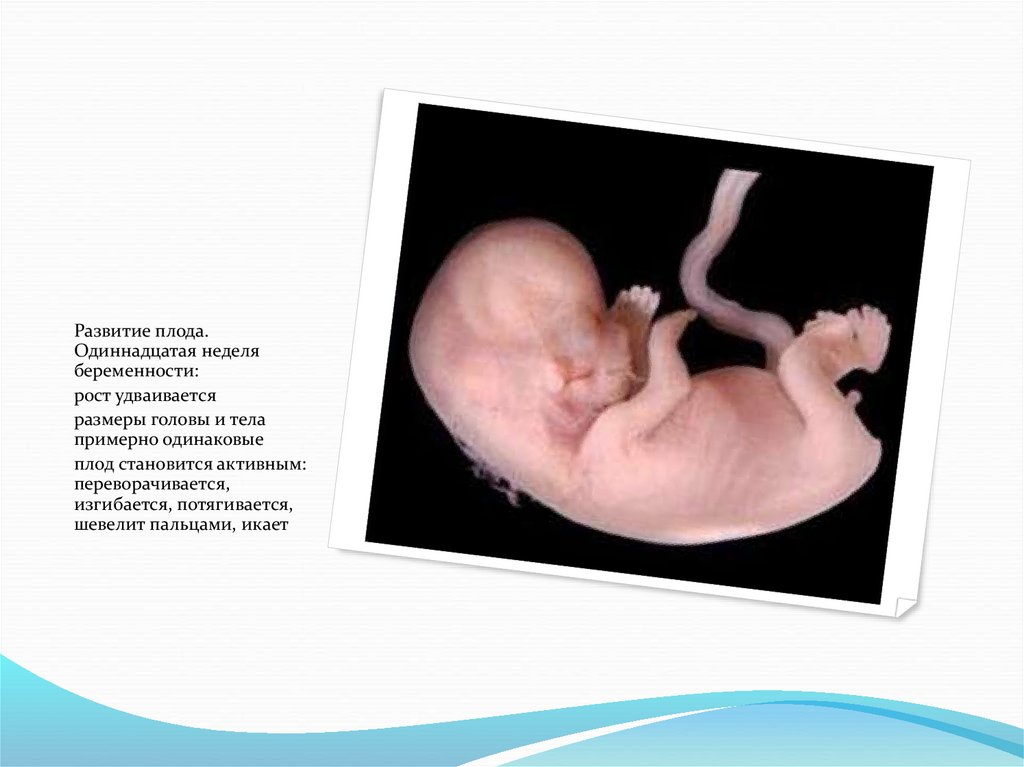

Развитие плода.

Одиннадцатая неделя

беременности:

рост удваивается

размеры головы и тела

примерно одинаковые

плод становится активным:

переворачивается,

изгибается, потягивается,

шевелит пальцами, икает